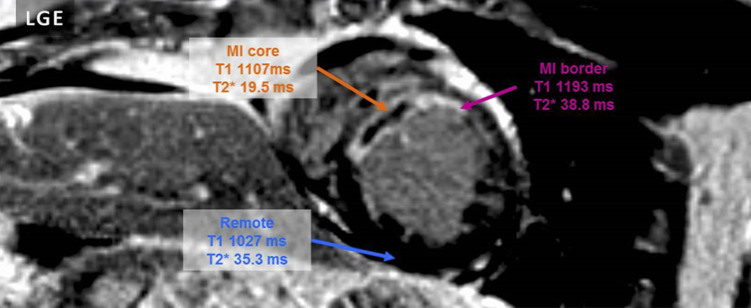

La cartographie IRM T1 native et l'imagerie tardive de contraste au gadolinium offrent une vision détaillée du myocarde après un infarctus aigu du myocarde (IAM). L'IRM cardiovasculaire avec cartographie T1 est une nouvelle technique qui permet de mesurer directement les valeurs T1 dans le myocarde et a été proposée comme nouvel outil de représentation du myocarde infarci, sans recourir à des agents de contraste. D'autre part, des études utilisant le contraste tardif au gadolinium ont montré que le myocarde infarci est constitué de tissus hétérogènes, parmi lesquels des myocytes rompus ou une altération plus grave du myocarde, accompagnés d'une hémorragie et/ou d'une obstruction microvasculaire. Les chercheurs ont évalué, dans cette étude, les effets des répercussions microvasculaires de l'IAM ainsi que de l'hémorragie intramyocardique sur les valeurs T1 et T2 * locales, chez les patients avec un infarctus reperfusé.

Quarante-trois patients après IM reperfusé ont subi une IRM cardiovasculaire à 4 [3-5] jours, avec des séquences de cartographie MOLLI T1 et T2 *, STIR, ciné et contraste au gadolinium. Après administration de produit de contraste, l'imagerie fonctionnelle a été réalisée en utilisant une séquence d'imagerie cinétique avec gating ECG rétrospectif et apnée, selon des coupes de petit axe. Au moins 10 minutes après l'administration du produit de contraste, des images ont été acquises en utilisant une séquence d'impulsions d'écho de gradient. Les valeurs de T1 et T2 * ont été déterminées dans des régions d'intérêt définies par l'imagerie de contraste: le noyau de l'infarctus, les zones adjacentes à celui-ci ou les affections microvasculaires notamment.

Sur les 52 patients initialement retenus, neuf ont été exclus de l'analyse en raison de la qualité insuffisante des cartographies T1 ou T2 *, principalement par défaut d'apnée. Cette étude a montré que la densité moyenne en T1 dans le noyau de l'infarctus était plus élevée que dans la zone adjacente à celui-ci ou que dans le myocarde distant. Cependant, chez les 20 patients (47%) présentant une altération microvasculaire, la densité en T1 était plus sombre que pour les autres patients. Enfin, en T2 *, le noyau de l'infarctus montrait un contraste significativement plus faible chez les patients avec altération microvasculaire que chez les autres.

Cette étude confirme donc que les valeurs moyennes de T1 et T2 * évoluent dans la zone affectée à la suite d'un œdème lié à l'infarctus, les lésions microvasculaires montrant une diminution des valeurs T1 et T2 * dans le noyau de l'infarctus. Cela a des implications pour l'interprétation des valeurs de cartographie T1 native peu de temps après l'accident car, sans l'utilisation appropriée de la cartographie T2 *, le myocarde avec atteinte microvasculaire peut être incorrectement classé comme normal et myocarde non affecté.